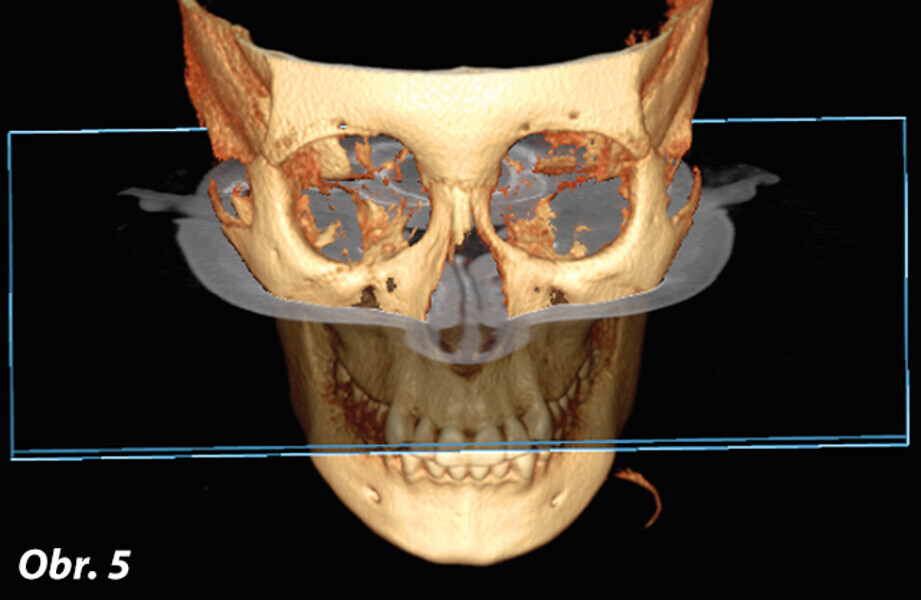

Význam 3D zobrazovacích systémů v současné ortodoncii